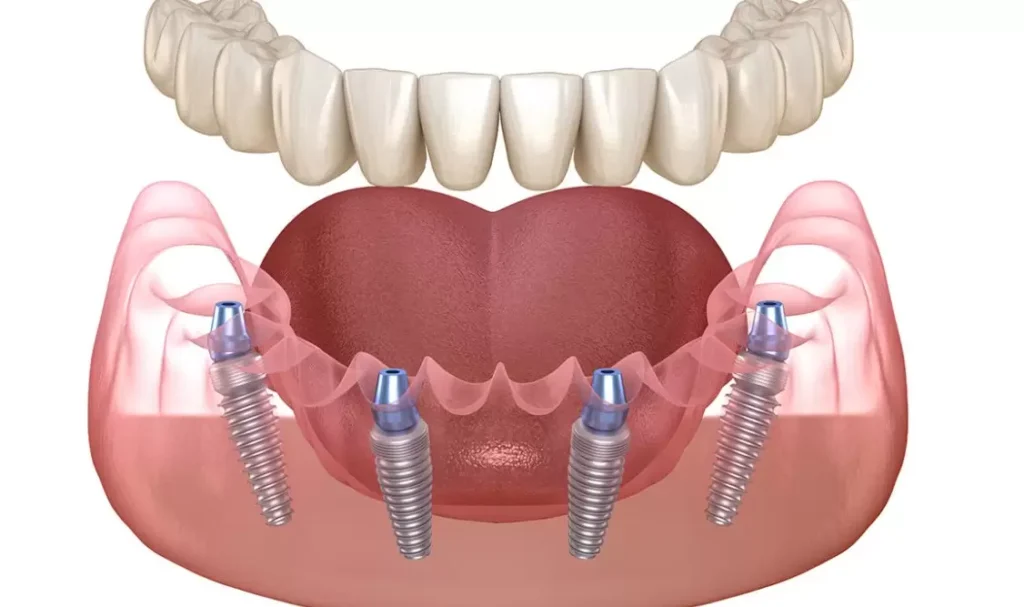

All on 4

All on 4 può creare una serie completa di denti utilizzando solo quattro impianti in ciascuna mascella. La fattibilità di ciò dipende dalla mascella e dalle circostanze specifiche. Una volta valutati i tuoi denti attuali, il livello di danno, nonché la struttura e la salute della mascella, possiamo stabilire se un impianto All on 4 è la scelta giusta. Questa procedura chirurgica utilizza otto impianti, quattro nella mascella superiore e quattro nella mascella inferiore, per supportare protesi o corone permanenti.